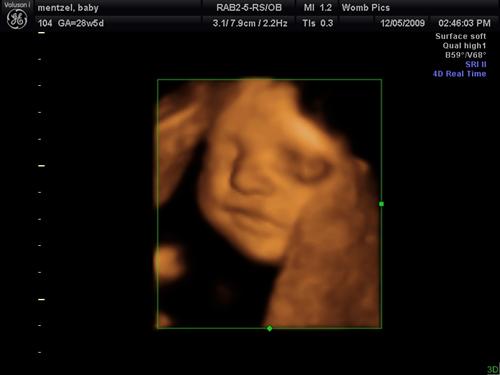

3/D - 4/D sonogram pics

Click a thumbnail to view fullsize image.